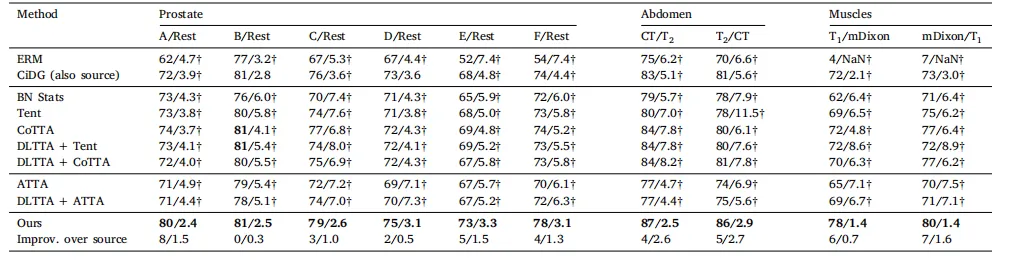

Table 1 Comparison on four datasets. denotes the results obtained by reproduced based on the publicly codes. The best and second-best results are marked in bold and underlined, respectively

表 1 四个数据集上的比较。表示基于公开代码复现所得的结果。最佳结果和次优结果分别用加粗和下划线标注。

We evaluated our method and other benchmarking methods onfive datasets of different types of medical images. Each dataset has aunique distribution due to images collected from multiple sites and/ormodalities. We describe each dataset in paragraphs below.The first dataset is a cross-site binary prostate segmentation datasetfrom T2 -weighted MRI scans collected from six different sites where12–30 scans were available for each site (Bloch et al., 2015; Lemaîtreet al., 2015; Litjens et al., 2014).The second dataset is a cross-site and cross-modality multi-class(liver, left and right kidneys, and spleen) abdominal segmentationdataset between 30 CT and 20 MRI T2 -SPIR scans (Landman et al.,2015; Kavur et al., 2021).The third dataset is a same-site cross-modality muscle segmentationdataset with 13 lower-leg muscles and bones between 30 MRI T1 andmDixon scans (Zhu et al., 2021).The fourth dataset is a cross-site and cross-modality whole braintumor segmentation dataset (Menze et al., 2015) from over 100 MRI T2FLAIR and T2 -weighted scans. The dataset was collected by two centers.The last dataset is a cross-site and cross-modality heart segmentation dataset of four substructures (left ventricle, myocardium, leftatrium, and ascending aorta) from 20 MRI balanced steady-state freeprecession (b-SSFP) and CT scans (Wu and Zhuang, 2020).All scans were normalized to zero mean and unit variance beforebeing reformatted to 2D. Following other studies (Ouyang et al., 2023;Zhu et al., 2022; Wu and Zhuang, 2020), the prostate, brain tumor,and abdominal scans were resized to 192 × 192 pixels while the heartsubstructure and the muscle scans were center-cropped to 256 × 256and resized to 128 × 128 pixels, respectively. Lastly, a window of[−275, 125] in Houndsfield units was applied to CT scans and the top0.5% of the histogram of MRI scans was clipped.For the first dataset, we treated each site as the source domainand adapted to all other sites. The adaptation was performed in bothalphabetic and randomized orders. For example, the source model wasfirst trained on site A, then adapted to sites B, C, D, E, and F (alphabetic)and also adapted to sites F, E, D, B, and C (randomized). For otherdatasets, we first performed adaptation from modality A to B, then fromB to A. All experiments were performed in an online and continuoumanner: each test scan arrived randomly and was broken down intomultiple batches if needed. The model adapted itself to each batchbefore making a prediction. U-Net with an EfficientNet-b2 backbonewas used as the source model for all our experiments. We trained thesource model with ERM to provide a baseline model susceptible todomain shifts, and also with CiDG to produce another baseline thatis domain-generalized (i.e., resilient to domain shifts). Both baselinemodels were used by all the benchmarked adaptation methods toevaluate their efficacy in improving a baseline model’s target-domainperformance in various conditions. The Adam optimizer (Kingma andBa, 2015) was used with a learning rate of 0.001 and a batch sizeof 32. 𝛼 was set to 0.5 to achieve a balance between the local andglobal cross-task consistency terms, and 𝛽 was set to 1 to fully utilizethe self-regularization of the student model. 𝜅 was set to −1500 toapproximate the inverse transformation from the segmentation labelsto SDF maps, and 𝑝 to 0.01 to restore roughly 1% of model parametersback to their initial state with each gradient update. The model wasupdated for two steps (i.e., two gradient updates per test batch) forthe muscle, heart substructure, and brain tumor segmentation, fivesteps for the prostate segmentation, and ten steps for the abdominalsegmentation. The number of patches 𝑀 is determined by the slidingwindow size and its stride, which were empirically set to 48 and 32,respectively. 𝑁 was set to 12of 𝑀 to select the top 50% of patches withthe highest uncertainty scores to enforce effective local cross-task regularization while maintaining a reasonable computational efficiency.All hyperparameters except for the number of gradient update stepsare shared across all datasets. Our methods were implemented usingPyTorch 1.10.0 and trained on one Nvidia Tesla V100 GPU.2In addition, we calculated the final performance of each modelby using each model to re-predict the segmentation labels of all testsamples after the adaptation was completed. We then compared thefinal performance of each model against their running performanceto evaluate their ability for continual adaptation. Here, the term ‘running performance’ represents the cumulative evaluation metric scorescalculated from results produced by the model after each test batchwhile the adaptation was ongoing. On the other hand, the ‘final performance’ refers to the scores calculated from the results produced by the‘adapted’ model in one go after the adaptation had been completed. Theperformance was quantitatively evaluated by their volume-wise DiceSimilarity Coefficient (Dice, in %, the higher the better) and AverageSymmetric Surface Distance (ASSD, in mm, the lower the better).The statistical significance between results was determined with theWilcoxon signed-rank test at the pixel level. The significance thresholdwas set to 0.05.Lastly, we performed the adaptation at both the domain level(i.e., continuous adaptation) and single-image level to highlight thevalue of continuous adaptation. When performing the adaptation at thesingle-image level, the model was adapted to each test batch beforere-initializing its weights for the next test batch, whereas the model’sweights were continuously updated throughout the adaptation processfor the domain-level adaptation.